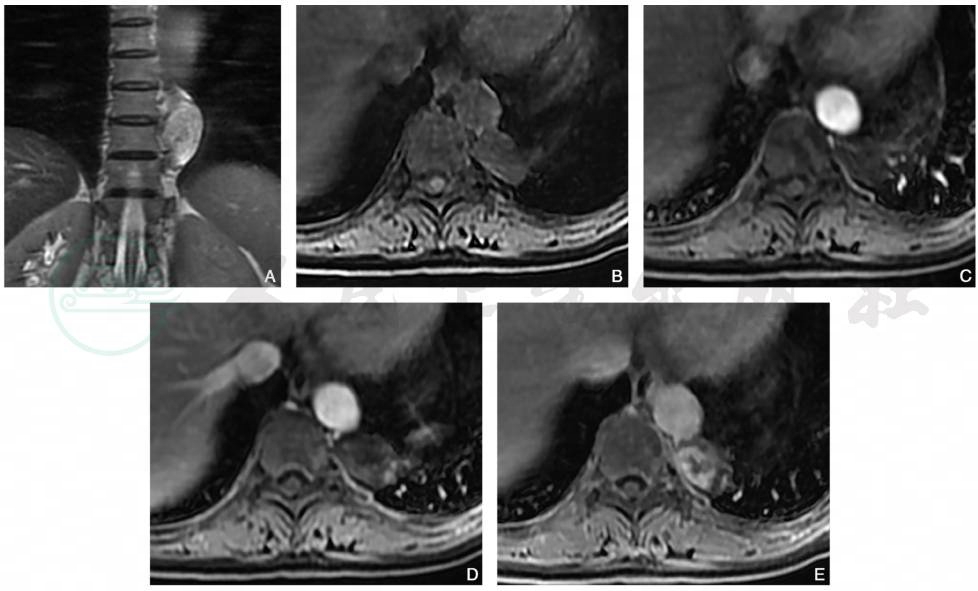

图11 神经鞘瘤

女性,58岁,冠状位T2WI(A)显示椎体左侧类圆形高信号,T1WI(B)呈低信号,增强扫描动脉期(C)病灶未见强化,静脉期(D)呈边缘轻度不均匀强化,延迟期(E)呈显著周边不均匀强化